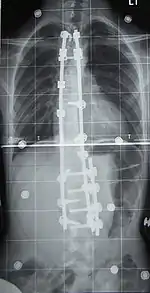

Surgery

Surgery is usually recommended by orthopedists for curves with a high likelihood of progression (i.e., greater than 45 to 50° of magnitude), curves that would be cosmetically unacceptable as an adult, curves in people with spina bifida and cerebral palsy that interfere with sitting and care, and curves that affect physiological functions such as breathing.[70]

Surgeons who are specialized in spine surgery perform surgery for scoliosis. To completely straighten a scoliotic spine is usually impossible, but for the most part, significant corrections are achieved.[72]

The two main types of surgery are:

- Anterior fusion: This surgical approach is through an incision at the side of the chest wall.

- Posterior fusion: This surgical approach is through an incision on the back and involves the use of metal instrumentation to correct the curve.